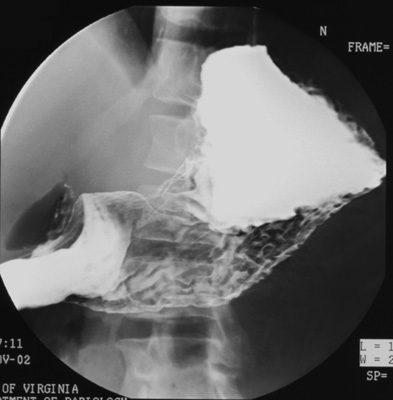

- RPO (First, turn patient into right lateral position

and elevate head of table 15 degrees to keep barium from flowing back into

gastric fundus as he rolls back into RPO position.)

- Right lateral (Wait until duodenal C-loop is

sufficiently filled with barium; otherwise, take this film at end of

study.)